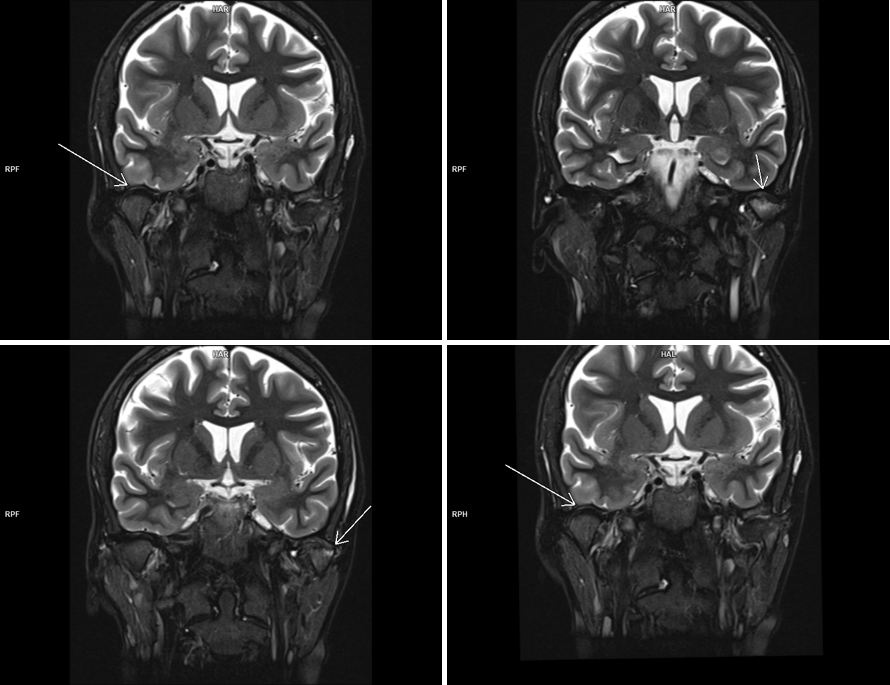

Figura 3: achiziţie oblic coronal T2 cu saturaţia grăsimii în planul articulațiilor temporo-mandibulare

Pe imaginile și secvențele cine prezentate se evidențiază modificare de formă a condilului mandibular stâng ce şi-a pierdut sfericitatea şi asociază prezenţa de modificări de tip edematos-inflamator în osul subcondral – modificare apărută probabil datorită unei asimetrii dentare astfel încât apare incongruența suprafețelor articulare iar pacientul prezintă cracmente articulare și blocare periodică a articulației; în principiu, asimetriile dentare (mușcături incorecte) duc în timp la probleme ale articulației, din cauza faptului că articulația este foarte mult solicitată.